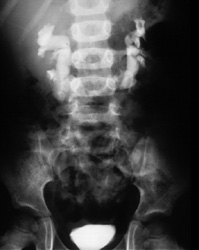

| Intravenous Pyelogram of Horseshoe Kidney This is an intravenous pyelogram (IVP) of a 10-year-old boy with a horseshoe kidney. The x-ray was obtained because he had hematuria after suffering a blow to the abdomen. Notice that the kidneys lie slightly lower in the abdomen than normal kidneys. As the fused lower poles of the horseshoe kidney ascend to the level of the inferior mesenteric artery, further ascent is halted. | ![]() |

| Horseshoe kidneys have an abnormal axis. Draw a line between the uppermost calyx and the lowermost calyx on each side. In normal kidneys this line will be closer to the vertebral column at the upper pole. In horseshoe kidneys, the line will be closer to the vertebral column at the lower pole. | ![]() |